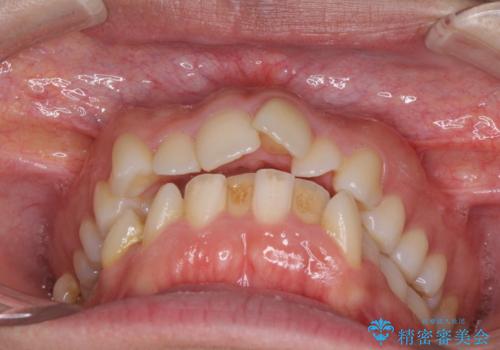

- 前歯のデコボコと口元の突出感を気にして来院された患者様です。

上下左右第一小臼歯4本を抜歯し、ワイヤー装置にて口元を引っ込めるよう矯正治療を行うこととしました。

叢生が強かったため、口元の突出感の改善には限界がありましたが、横側からも口元が引っ込んだ感じが分かるほど改善されました。